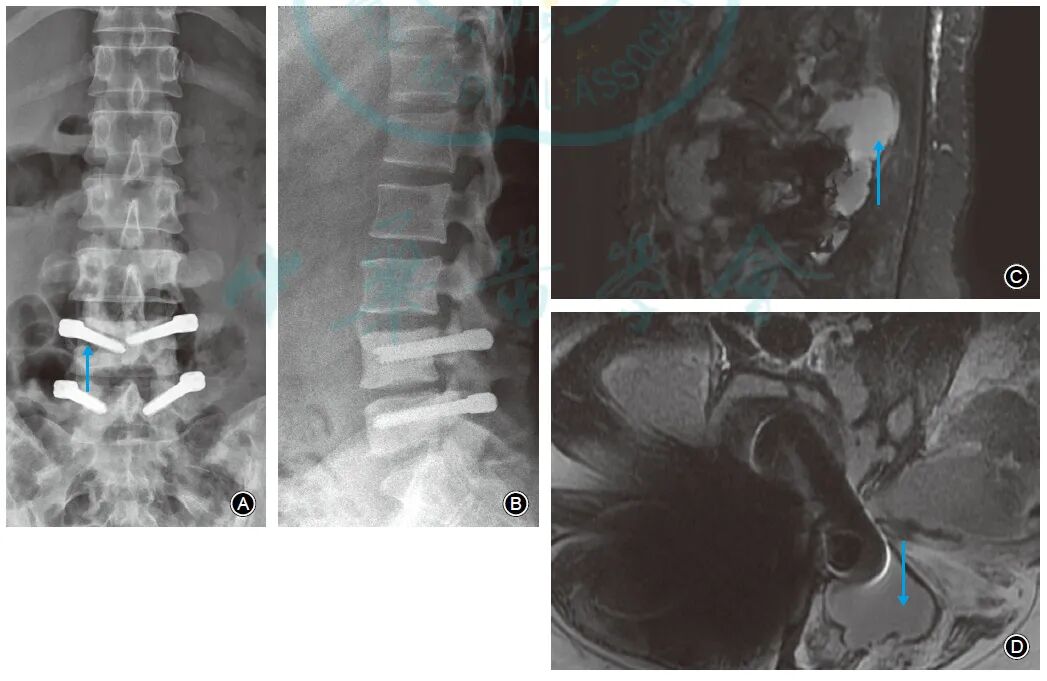

X线表现为螺钉周围骨质吸收、内固定松动11例。MRI表现为椎弓根螺钉周围积液者23例、椎旁积脓及腰大肌脓肿者1例(图1)。

图1 女,40岁,腰痛伴左下肢疼痛4d。3年前行L4-5椎间盘髓核摘除及Dynesys动态内固定,有糖尿病病史。白细胞计数为18.88×109/L,中性粒细胞比例0.91,C反应蛋白170.00mg/L,降钙素原0.35ng/ml,红细胞沉降率120.00mm/1h。诊断为腰椎内固定术后晚期感染,予以内固定取出。A腰椎正位X线片示L4椎弓根螺钉周围骨质吸收、内固定松动(箭头所示);B腰椎侧位X线片示L4椎弓根螺钉周围骨质吸收、内固定松动,L4,5椎体骨质硬化;C腰椎MRI矢状面脂肪抑制像示椎旁积脓(箭头所示);D腰椎MRI横断面T2WI片示椎弓根螺钉及间隔器周围积脓伴双侧腰大肌脓肿(箭头所示)